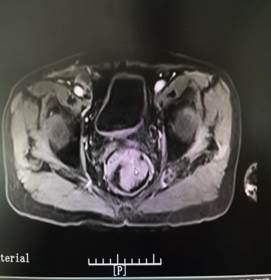

肛门指检,顾名思义,是一种通过医生手指触诊肛门及直肠的临床检查方法,用于筛查距肛缘7~10厘米内的病变,尤其对直肠癌等疾病的早期发现具有重要意义。就是这不起眼又略带尴尬的检查,往往救人于水火,成为很多患者的护“菊”使者,保“菊”先锋。因为许多肛管直肠疾患可以通过肛门指检早期发现,如70%到80%的直肠癌可在肛门指检时被发现,还有像痔疮、肛裂、直肠息肉、肛瘘、肛门直肠周围脓肿、肛乳头瘤、盆腔脓肿、骶前囊肿等疾病也能起到良好的辅助诊断作用,同时对于评估肛门括约肌功能,是否存在失禁问题也能及早诊断,男性还能排查前列腺疾病,比如前列腺炎、增生甚至前列腺癌,不少女性的子宫、盆腔肿瘤也能在肛门指检中甄别发现,可谓是性价比极高的“金手指”检查项目。

肛瘘可摸到索状物,有时在肛瘘内口可扪及小硬结。肛门直肠周围脓肿如骨盆直肠间隙脓肿、直肠后间隙脓肿,在直肠内可摸到压痛性肿块,并可能伴有波动感。指检时剧烈触痛者多见于肛裂及感染。